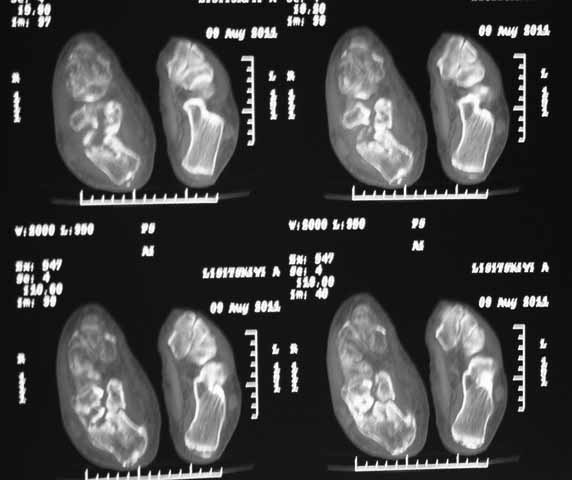

КТ перелома пяточной кости

Пациент 60 лет с производственной травмой-закрытые переломы правой пяточной кости, тибиального плато слева поступил в феврале с.г. На 4 сутки выполнена открытая репозиция, остеосинтез внутрисуставного перелома голени, ручная репозиция пяточной кости. Через три месяца начал ходить с нагрузкой на обе ноги. Консолидация голени с полным восстановлением функции колена. Правая стопа умеренно отечна, продольно распластана, длительная ходьба вызывает боли и увеличение отека. Прошел несколько курсов ударно-волновой терапии, грязелечение, боли и отек уменьшились. В наших планах -оформление на ВТЭК, через год возможно выполнение подтаранного артродеза.Но после производства КТ в августе появились сомнения в консолидации перелома.Ранее у нас не было опыта КТ переломов стопы и сканы привели в замешательство.Прилагаю снимки со дня поступления, августовские пациентом не представлены.С благодарностью примем советы коллег.